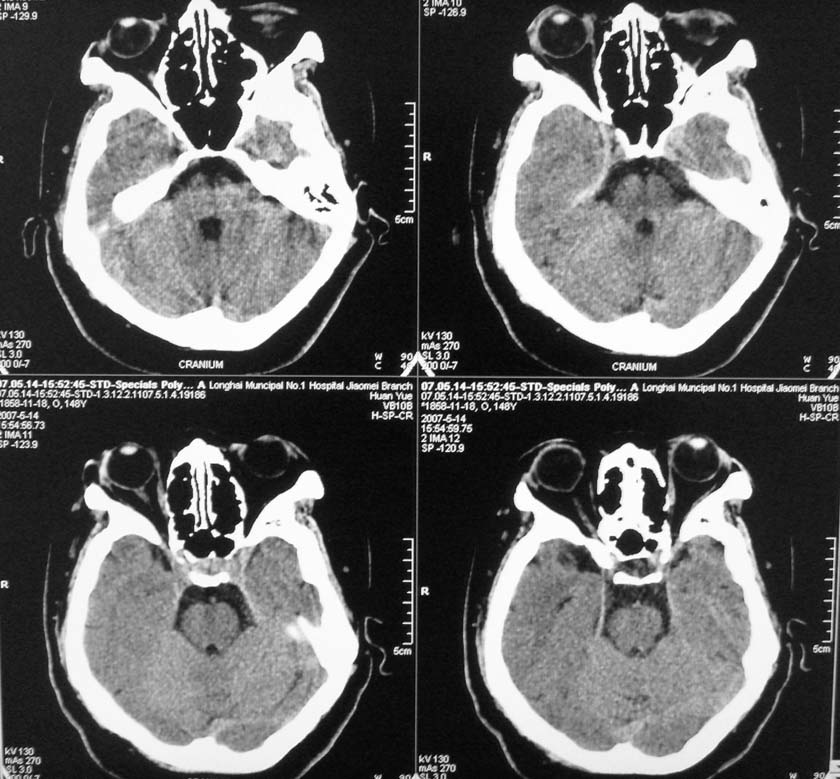

以下是引用天南地北在2007-5-15 23:30:00的发言:[br]看不出来什么[br]建议冠面增强扫描,或mri检查

以下是引用郭凯在2007-5-16 0:17:00的发言:[br]看不到,如果临床支持的话还是做mri看一下吧,对垂体微腺瘤比较敏感.[br]ct上看不到不能乱报.

以下是引用jiangjing在2007-5-16 11:06:00的发言:[br]看不出来什么[br]建议冠面增强扫描,或mri检查